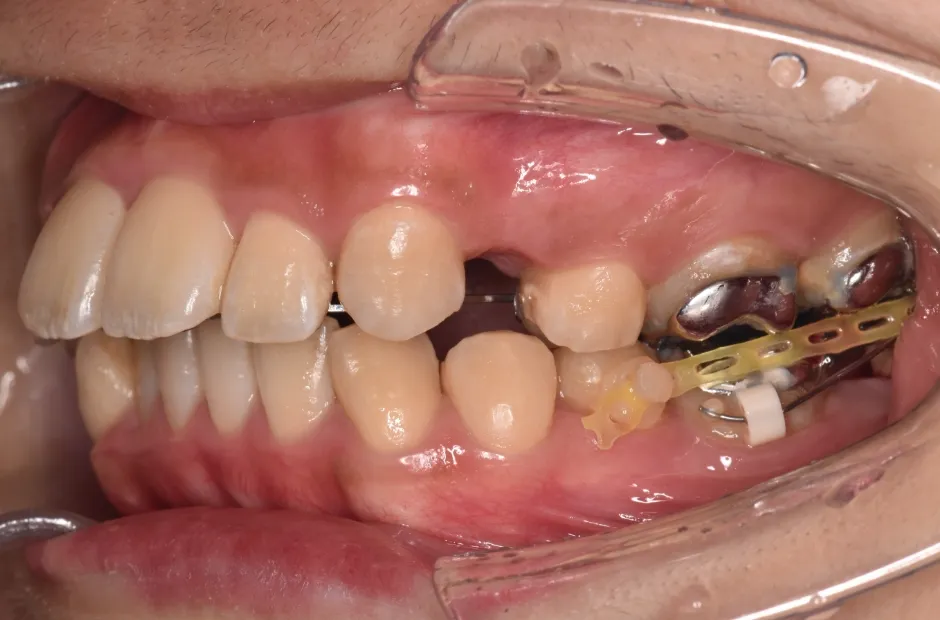

| 診断名・主訴 | 下顎前突、叢生 |

|---|---|

| 年齢・性別 | 23歳・女性 |

| 治療期間・回数 | 3年 |

| 治療に用いた主な装置 | 上顎5,5 下顎4,4 |

| 抜歯部位 | 舌側矯正 |

| 治療費 | 100万円(税抜) |

| リスク・副作用 | 装置による違和感・疼痛・歯肉退縮・歯根吸収・虫歯のリスクなど |

治療中